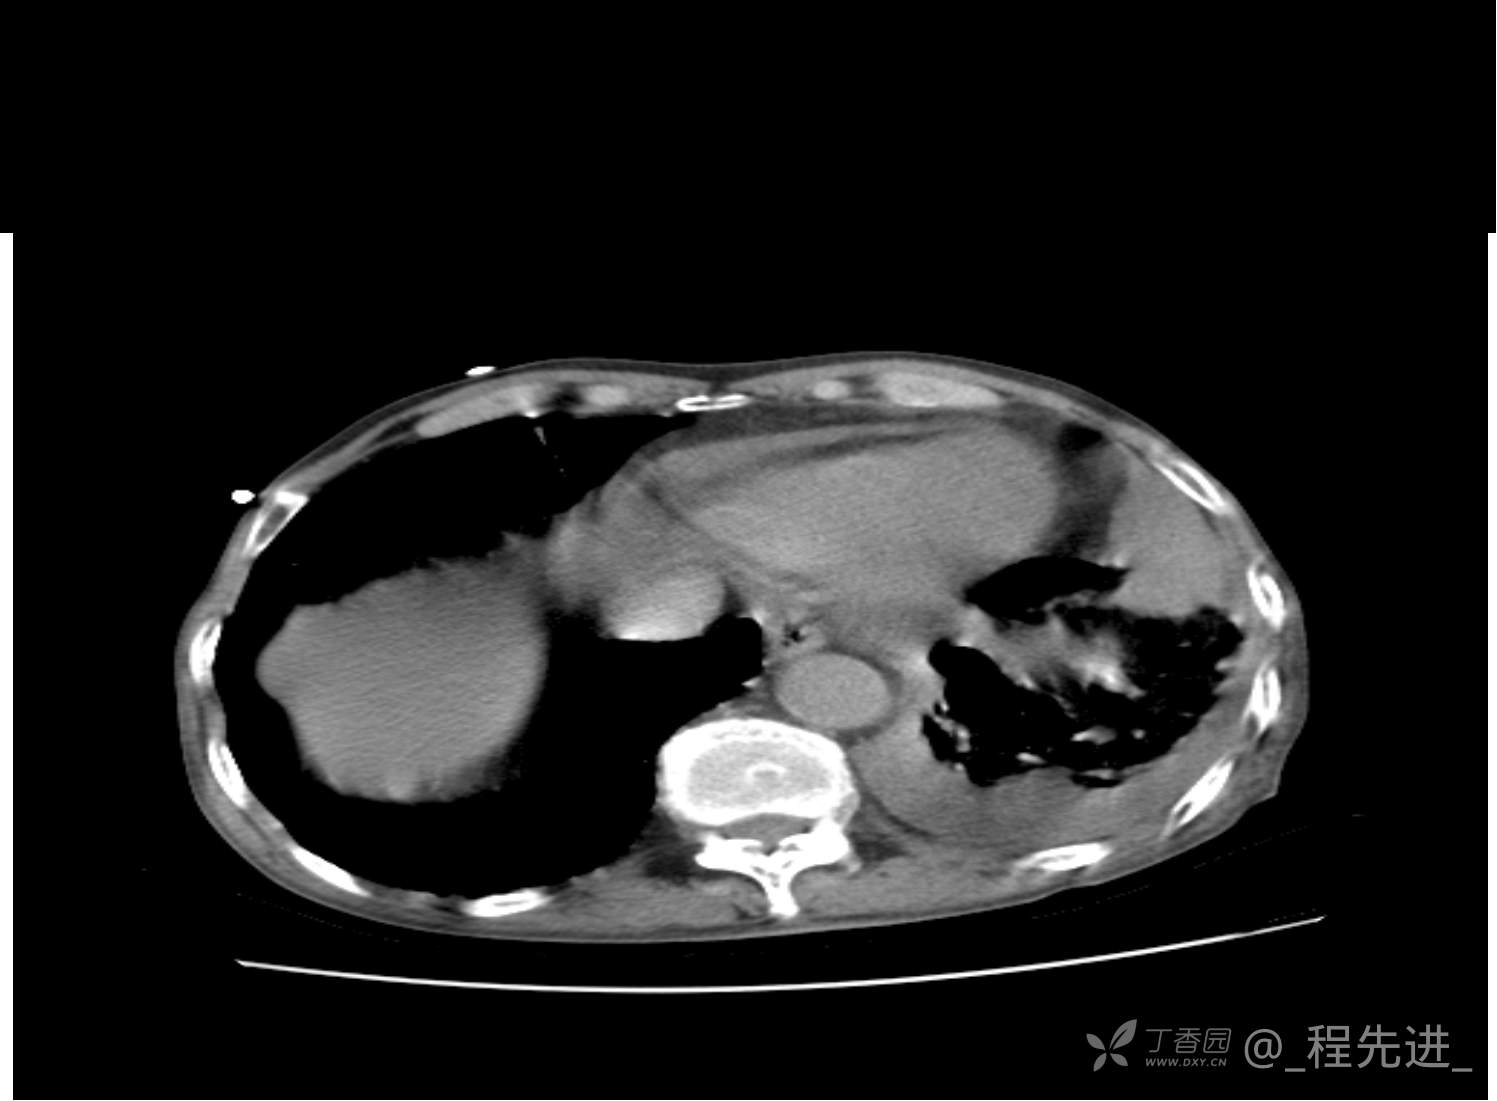

患者性别:男

患者年龄:81岁

简要病史:反复咳嗽、咳痰20余年,加重1周。两肺呼吸音低,可闻及散在干湿啰音。